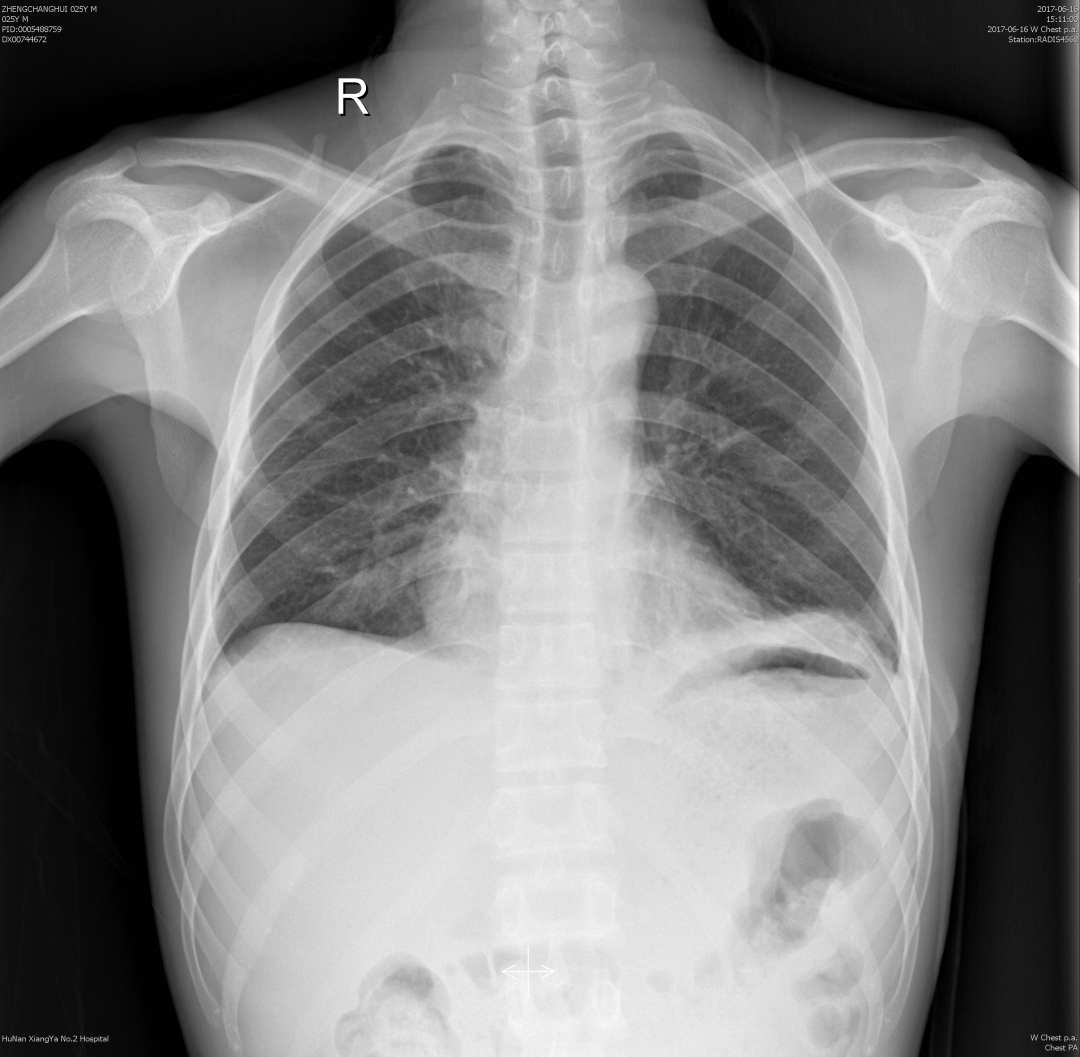

小马的肺部ct

完善胸部CT后,小马确诊为“自发性气胸”,气胸量较大,考虑可能为呼吸道病毒感染后发生肺部病变,剧烈运动诱发了自发性气胸。收住院进行治疗5天后复查胸片,气胸已基本吸收,小马转危为安。